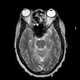

Paranasal sinusitis

Sinusitis, also known as rhinosinusitis, is inflammation of the mucous membranes that line the sinuses resulting in symptoms that may include thick nasal mucus, a plugged nose, and facial pain. Other signs and symptoms may include fever, headaches, a poor sense of smell, sore throat, and a cough. [Source: Wikipedia ]